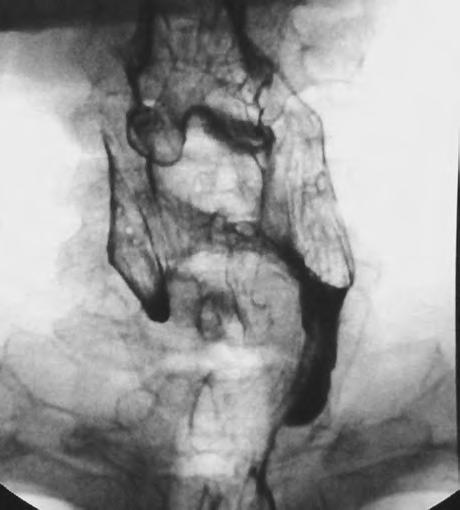

MeduloblastomsdalšímiprimitivnímineuroektodermálnímitumoryCNSpatříknejzhoubnějšímnádorůmdětskéhověku.Poleukemiíchjedruhýmnejčastějšímmalignímonemocněním.Nejčastěji vyrůstázdolní částivermis,infiltrujepostupně celou IV.komoruaněkdyprorůstáidomozečkovýchhemisfér.Infiltrujeměkképlenyametastazujevlikvorovémprostoruvšemisměry,zejménavšakdoprostorupáteřníhokanálu.Pooperacibrzyrecidivuje, aprotocílemoperacejezjistithistologickoudiagnózuazmenšitmasutumoru,anižbydošlokvětšímu poškozenínervovýchstruktur,vizobr.1.6.

1.6 Meduloblastom, v oblasti IV. komory v zadní jámě se může šířit implantačními metastázami vlikvorovém prostoru jak v intrakraniální oblasti, tak i na úrovni pateřního kanálu, viz šipky.